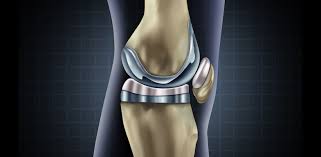

Acl reconstruction knee surgery involves replacing the torn anterior cruciate ligament with a new graft. See full list on practicalpainmanagement.com This is usually due to either the ligament not healing in a tight enough position or from associated damage inside the knee. Tailored rehab programmes and wearing an acl bracecan help with this. When the tear's bad enough, rest and rehab therapy aren't enough to repair an acl.

It is important when resting with your leg elevated not to have anything underneath your knee as you want to be stretching it out 5. Phase three on the acl surgery recovery timeline is when the knee is most vulnerable. This is taken either from your own tissue (autograft), or from donor tissue (allograft). People usually recover really well after acl surgery, but many report a few problems in the early stages. Knee pain some pain after acl surgery is common both at the knee itself and around the new graft area but it is usually quite tolerable. The alternative methods are listed below. Most patients can expect to play sports and exercise at a high level. The main risks with acl knee surgery are: Acl reconstruction knee surgery involves replacing the torn anterior cruciate ligament with a new graft. Numbness numbness around the scars is common due to damage to the small nerves around the knee from the incisions. It typically takes seven to 10 days after the procedure, until the patient is comfortable without the assistance of a crutch. See full list on practicalpainmanagement.com Discomfort while walking the diagnosis of an acl injury can be confirmed by physical examination, which includes comparing the injured to the uninjured knee to help determine the state of the acl.